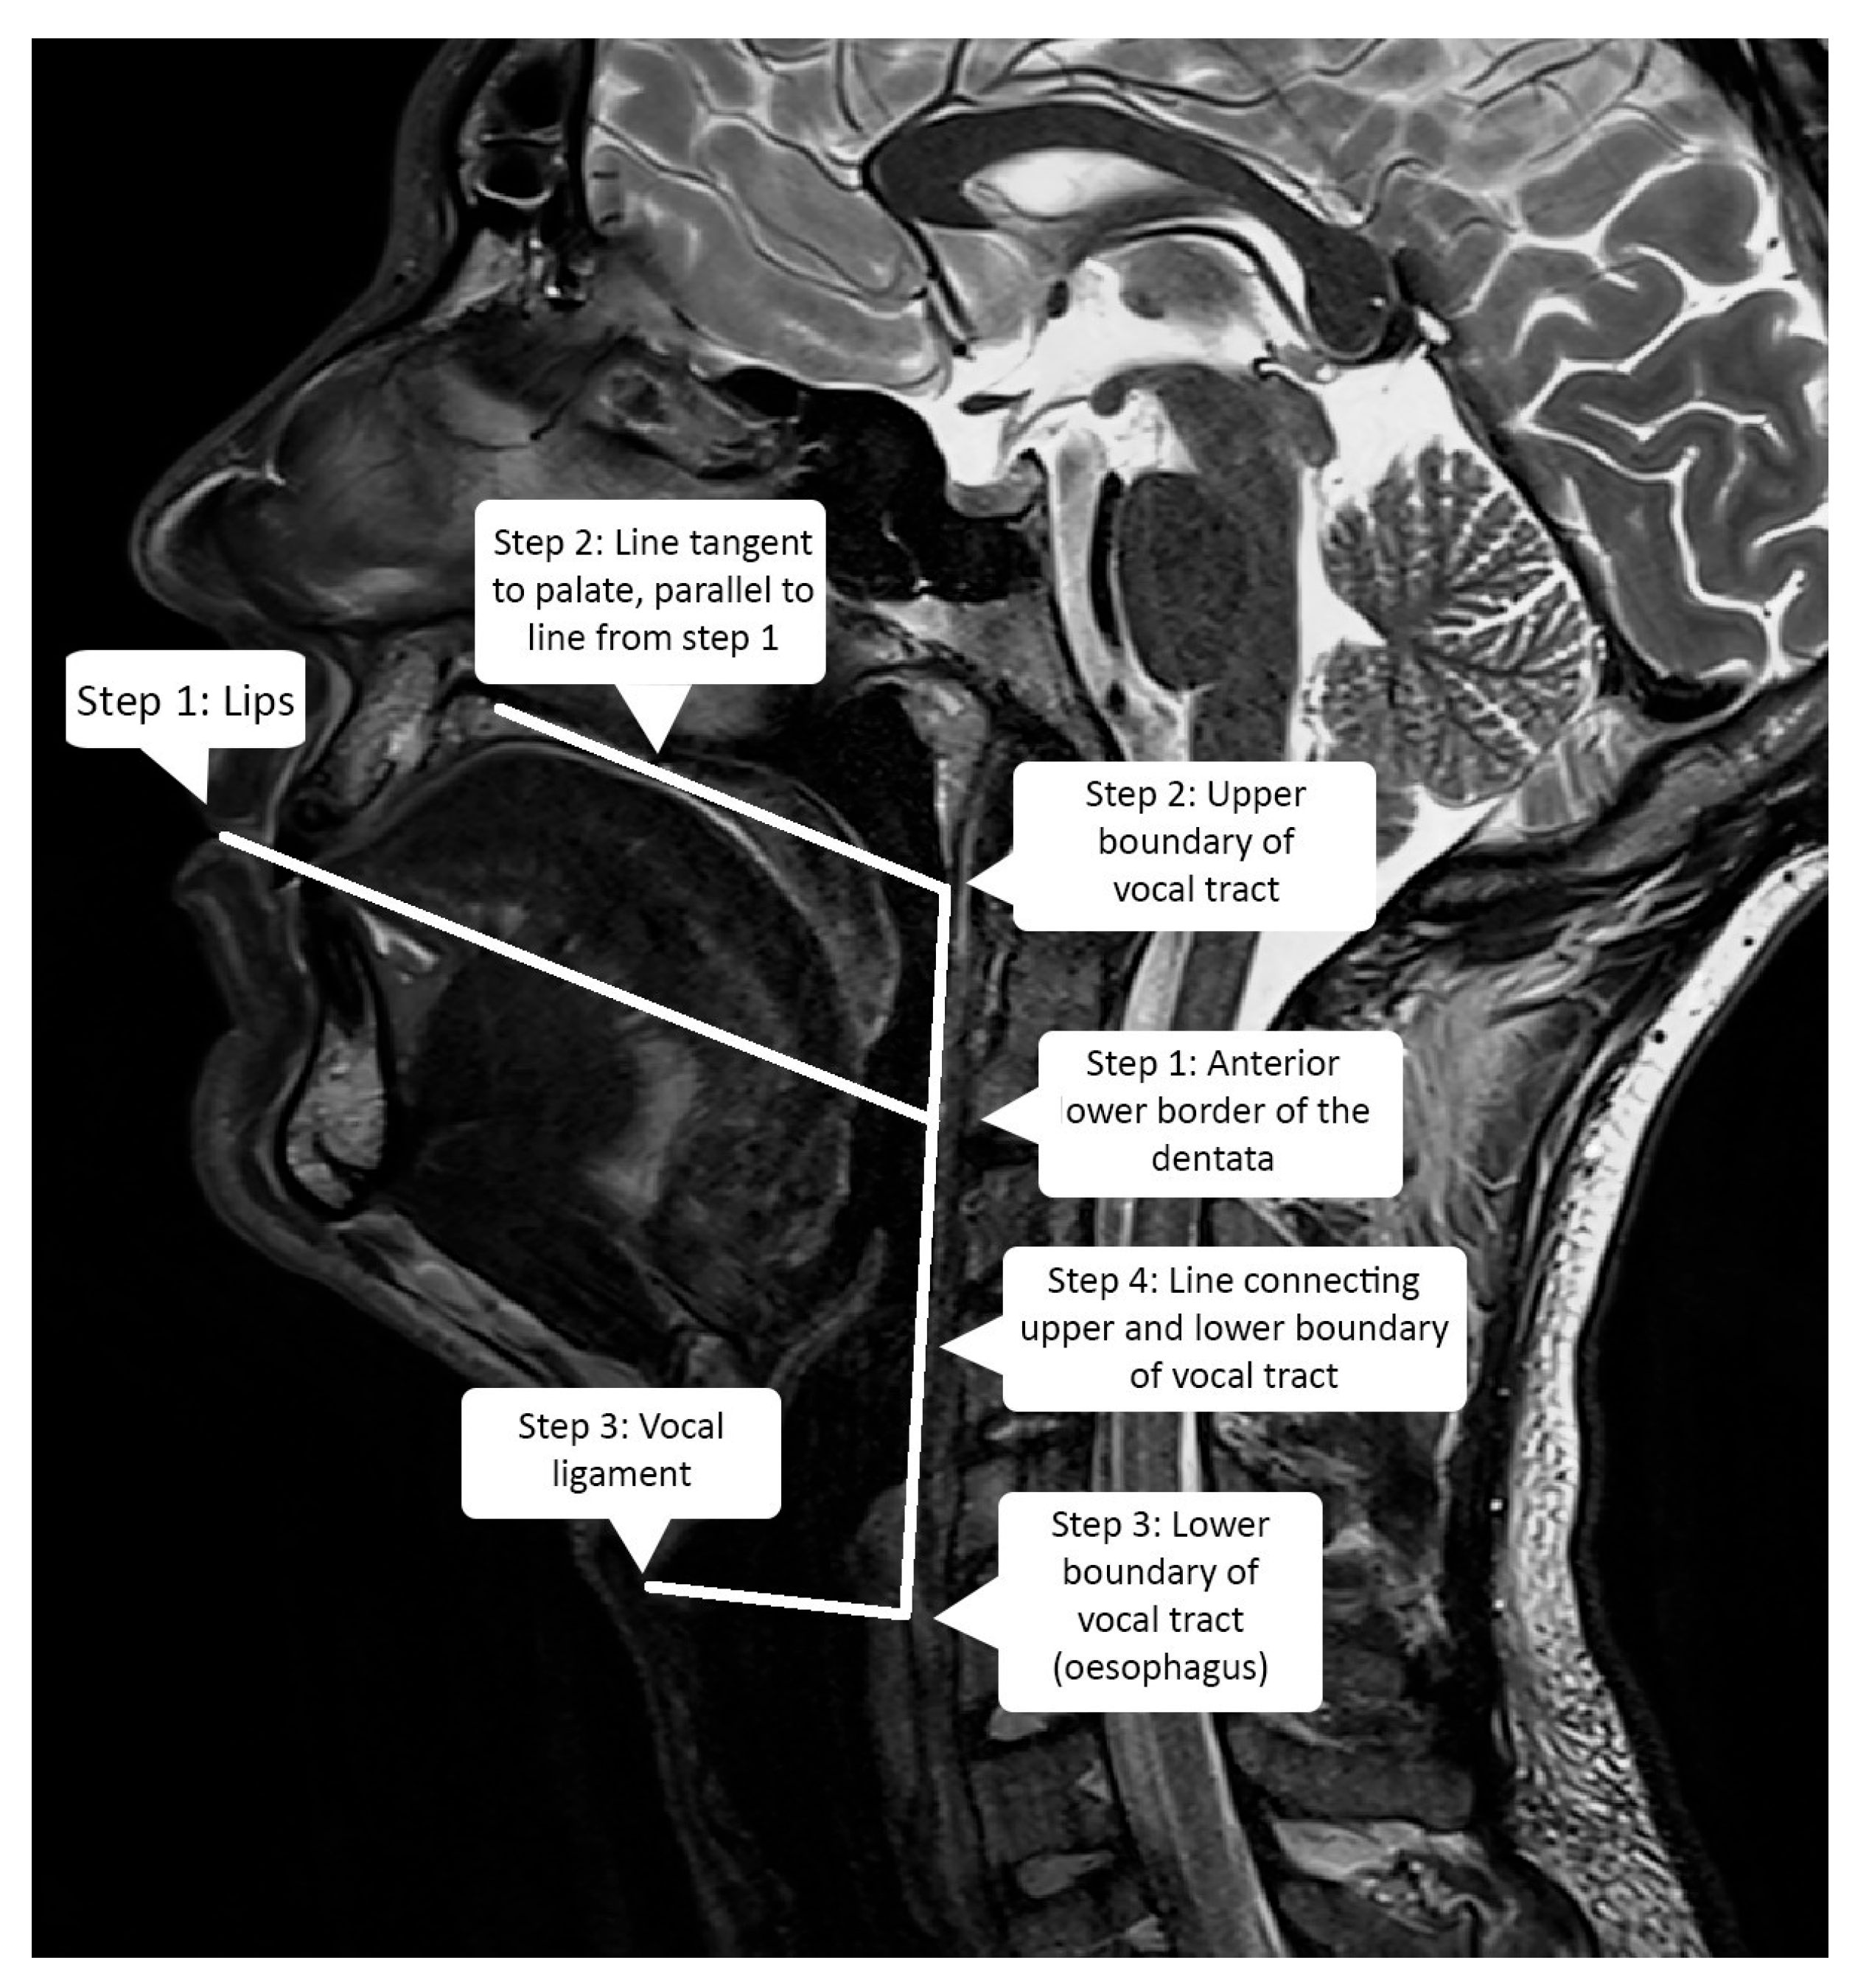

2.3. Vocal Tract Measurements